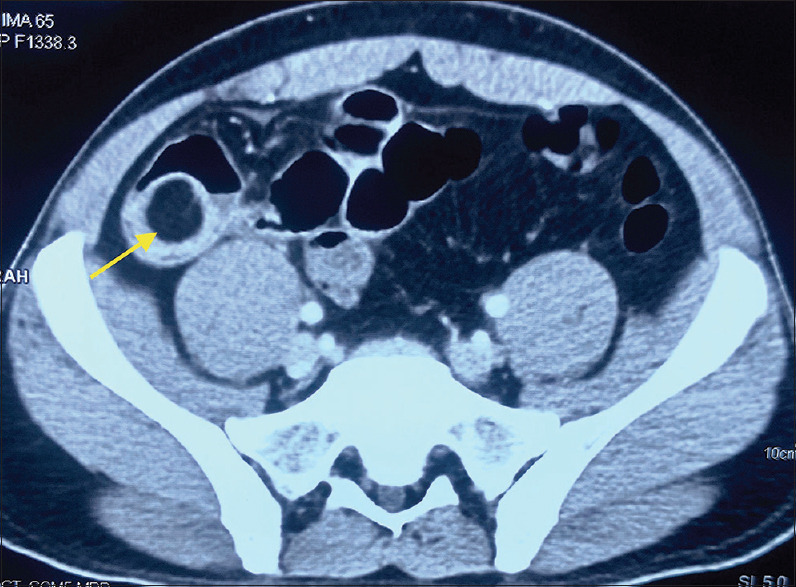

Abstract: Small bowel lipomas are benign submucosal neoplasm composed mainly of mature adipose tissue. Despite their rare occurrence, lipomas are the second most common benign tumour of the small intestine. These tumours are mostly small in size and remain clinically asymptomatic. However, larger lesions tend to be more symptomatic, presenting with complications such as intussusception, bleeding or obstruction. Definitive surgical or endoscopic intervention is indicated in such symptomatic lipomas. Herein, we describe a rare case of ileal lipoma presenting with ileo-ileal intussusception and a life-threatening haemorrhage that was managed by laparoscopic-assisted ileal resection.

Abstract Image